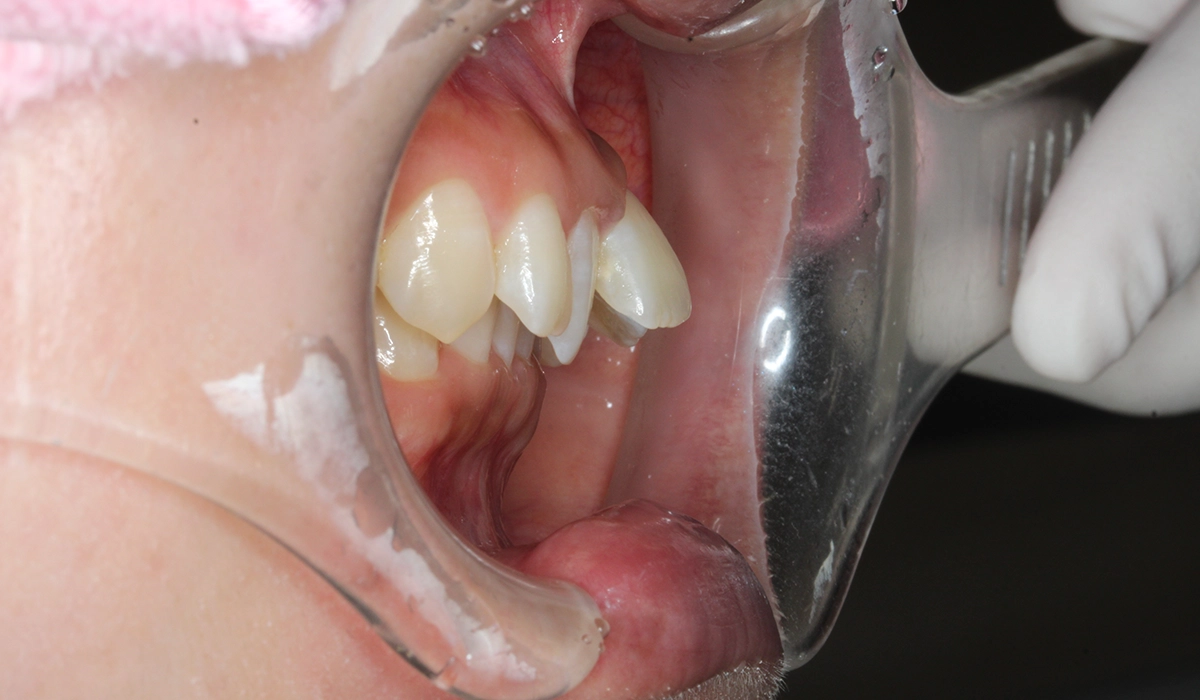

今回ご紹介する患者様は、前歯の噛み合わせの悪さ、歯並び、下の前歯が上の歯茎に当たることを気にされており、矯正検査後叢生Ⅰ級と診断いたしました。

術前:右側

術前:オーバージェット